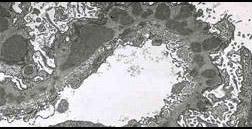

图-1 IgG沿毛细血管壁细颗粒状沉积,图-2免疫荧光显微镜所见:IgG和补体呈细颗粒沉积于肾小球毛细血管壁沉积,图-3电镜下,可见较暗的电子致密的免疫反...

问题 图-1 IgG沿毛细血管壁细颗粒状沉积,图-2免疫荧光显微镜所见:IgG和补体呈细颗粒沉积于肾小球毛细血管壁沉积,图-3电镜下,可见较暗的电子致密的免疫反应物质弥散分布在增厚的基底膜上。其病理可诊断 ( )

选项 A.膜性肾病 B.膜增生性肾小球肾炎 C.系膜增生性肾小球肾炎 D.局灶节段性肾小球硬化 E.毛细血管内增生性肾小球肾炎

答案 A